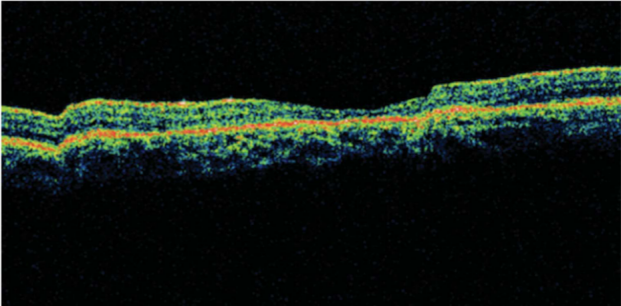

专科检查:右眼最佳矫正视力为20/100;左眼最佳矫正视力为20/40。眼前节检查无异常。两只眼睛的眼底检查均显示黄斑部有黄斑牛眼征,环形古铜色区域外有一圈紫红色(图 1 , 2)[1]

图2

遇到这样双眼黄斑牛眼征,首先考虑遗传性疾病,OCT和电生理检查肯定是少不了的。该患儿双眼的OCT扫描显示黄斑中心凹变薄,右眼更严重,感光器萎缩,RPE反射率增加(图3和图4)[1]。ERG显示熄灭型,而暗适应基本正常。如果考虑色素变性,该患儿没有描述夜盲症状,眼底彩照也没发现视网膜色素改变,仅仅是黄斑区牛眼征。

双眼OCT显示(图3,4)患者的中心凹变薄和感光细胞发生萎缩。该患儿在停止口服药物后,视力仍在进行性下降,推测持续升高的血清铁蛋白对视力造成更大的伤害。